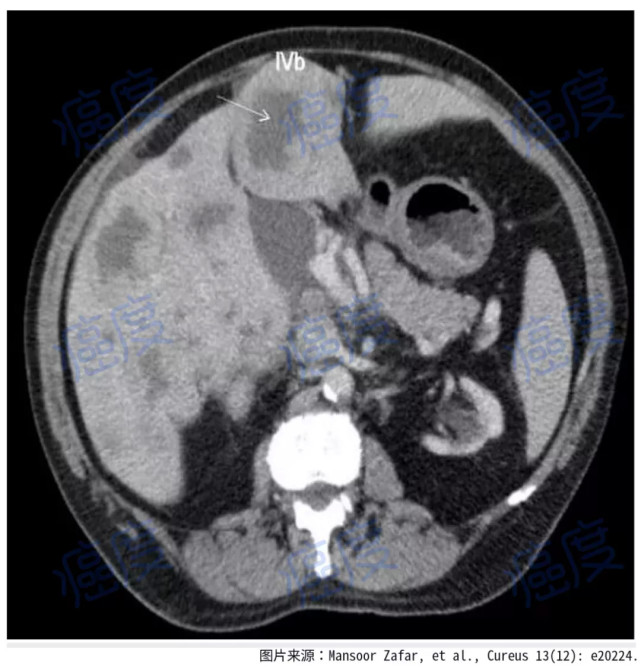

6年后患者再次进行胃镜检查,同时进行胸部、腹部和骨盆CT扫描。检查结果表明,除去胃小弯有一个小结节,胃镜没有发现任何恶性肿瘤的迹象,胃部小结节也仅仅显示为慢性胃炎。与6年前的CT扫描结果相比,肝转移灶的大小和数量显著减少。其他的器官没有发现转移性疾病的迹象。

图片图2.6年后的腹部CT显示病灶都消失了